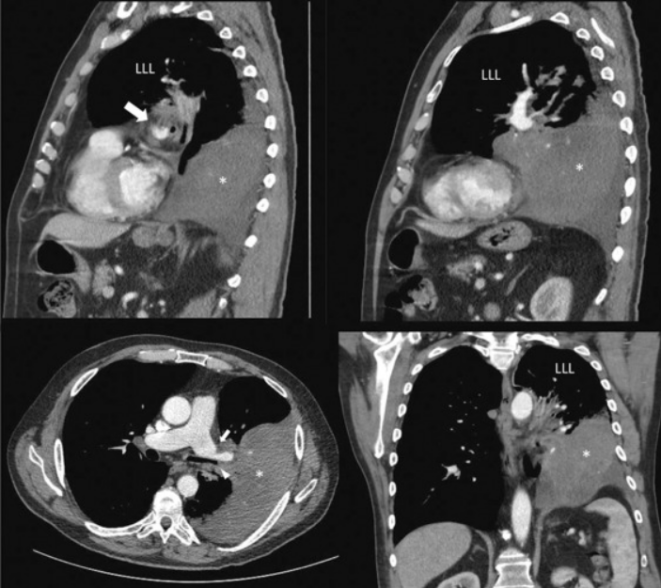

这“翻转”来的太突然,即使再次胸片检查也依旧如此。不得已行CT检查和三维渲染重建,见图3。胸部CT示右侧斜裂反转,中间支气管异常前行,肺血管旋转;右下肺动脉与中间支气管一起被拉向前行;右肺广泛实变,并伴有胸腔积液;外观显示右肺发生了180度扭转。

图3 胸部CT